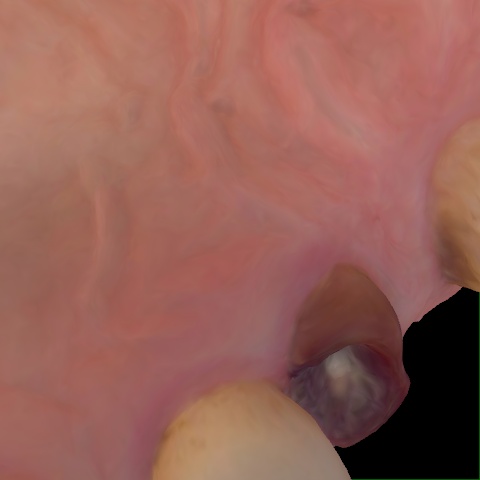

Annotated as "Good"